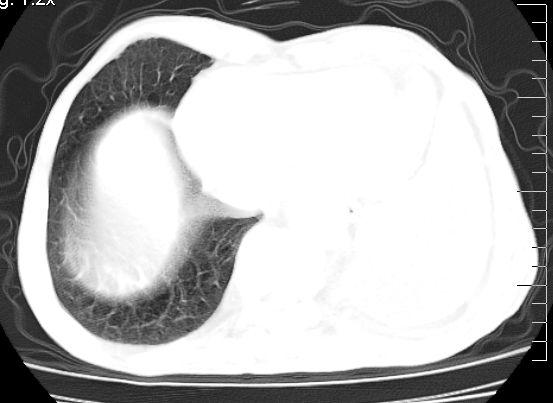

标题: CT10141:男、84岁,咳嗽、咯血1年。 [打印本页]

标题: CT10141:男、84岁,咳嗽、咯血1年。

支持左侧中央型肺癌伴下叶肺不张\\纵隔淋巴结转移.左侧包裹性胸腔积液\\心包积液.左侧少量胸腔积液..慢性支气管炎伴部分间质纤维化.

支持:左侧中央型肺癌伴下叶肺不张\\纵隔淋巴结转移.左侧包裹性胸腔积液\\心包积液.左侧少量胸腔积液..慢性支气管炎伴部分间质纤维化.另:支气管分支根部明显阻塞 狭窄,内膜凸凹不平,提示内膜增生物。

咯血病史较长,左肺下叶实变,体积未明显缩小,隐约可见血管影及坏死阴影,双肺门及纵隔淋巴结增大,心包增厚积液,纵隔右移位,单侧胸腔积液,首先考虑:大叶型肺泡癌伴纵隔心包转移。